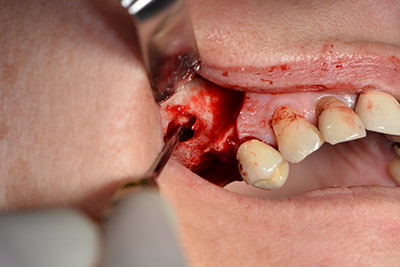

Dunque, l'impianto viene posizionato e l'osso ricostruito. In questo caso, considerate le dimensioni della regione di accrescimento, i microframmenti dell'osso autologo (raccolti con un'apposita cannula di aspirazione in seguito alla perforazione dell'impianto 16 e della fenestrazione 14) vengono combinati con dei materiali di riempimento dell'osso.

Una membrana riassorbibile viene usata come barriera in direzione buccale per contenere l'accrescimento. Infine, vengono applicate suture resistenti alla saliva (da fig. 15 a 19).